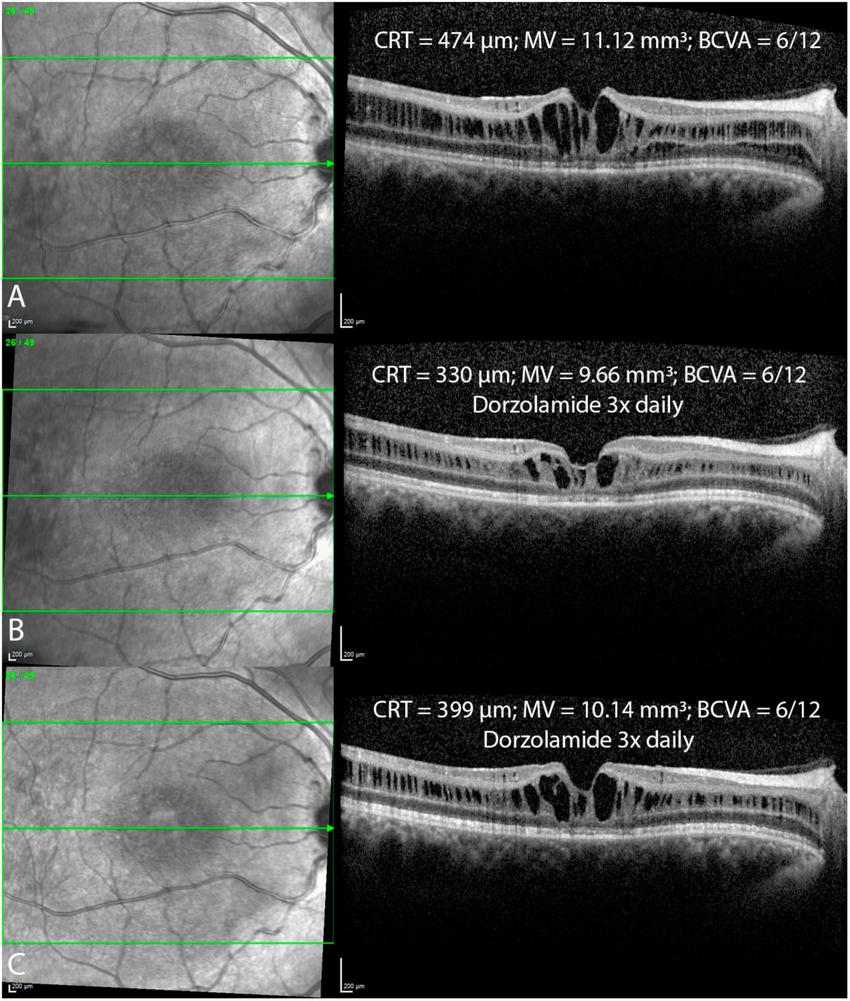

In our cohort of patients, several tested variables were associated with statistically significant CRT changes. Age at baseline: For every year in the age of patients at their baseline visit, CRT was 2.80 μm thinner (p = 0.0077). Time since baseline: The estimated rate of progression was −4.94 μm/year (p = 0.0156). Pharmacologic treatment: Treated retinas were overall 41.2 μm thicker, compared to untreated retinas (p = 0.0257). As expected, laterality was not a significant factor (−5.88 μm in right eyes, p = 0.4478). In addition, pharmacological treatment did not significantly influence the yearly change of CRT (Δ + 1.92 μm/year in untreated eyes compared to treated eyes, p = 0.3394) (Figure 5). Fluctuations in ICC were observed in patients under continuous treatment with CAI (Figure 6).

FIGURE 6

Foveal optical coherence tomography (OCT) scans in a patient before (A) and after the topical treatment with dorzolamide drops 3x daily (B,C) over a one year follow up period reveal fluctuations in intraretinal cystoid cavities, with ongoing treatment. Central retinal thickness (CRT); macular volume (MV); best corrected visual acuity (BCVA).